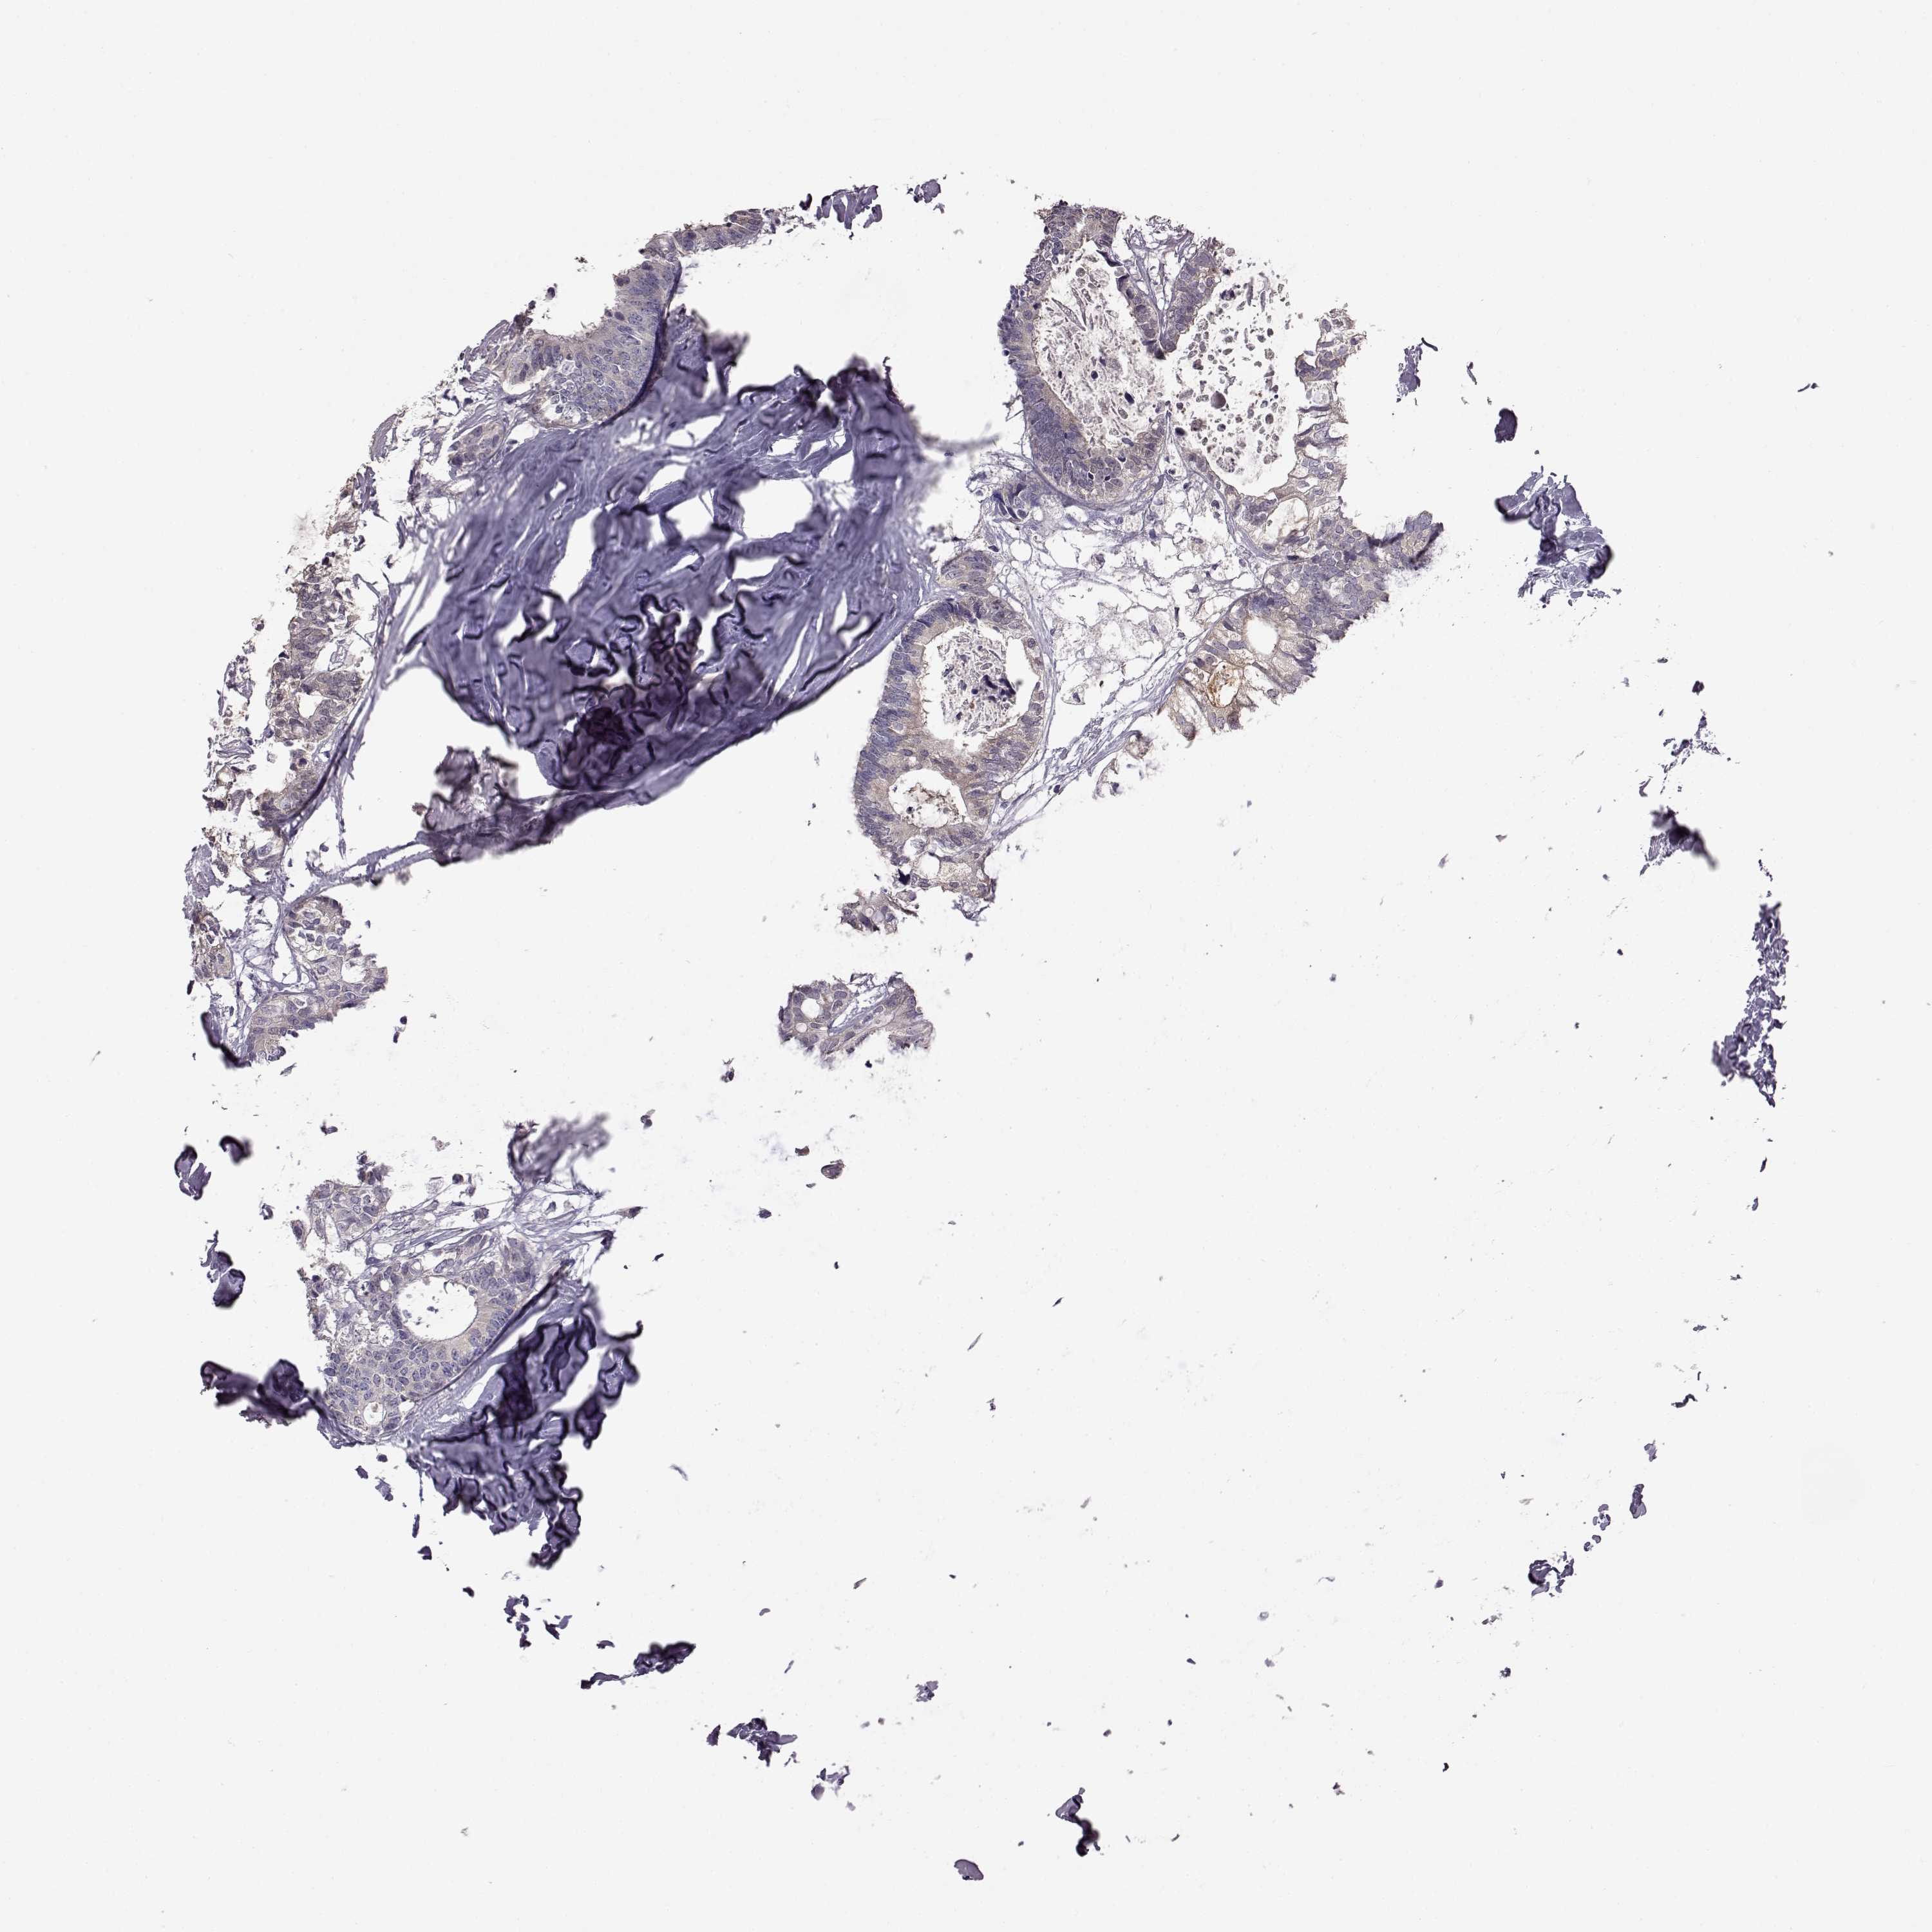

CANCER COLORECTAL CANCER Show tissue menu

Colorectal cancer

Rectum adenocarcinoma